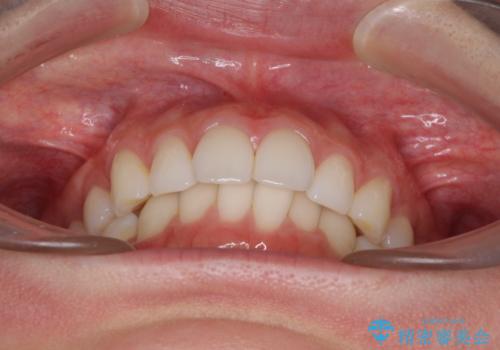

- 上下前歯の叢生を気にして来院された患者様です。

以前矯正をした後戻りということで、歯列不正はそれほど大きくなかったため、インビザライン・ライトを用いて矯正治療を行うこととしました。

前歯のデコボコが残っており、シミュレーション通りに動いていない部分がありましたが、再矯正であることやご本人の満足いくところまでデコボコが改善されたとのことで、治療を終了することとしました。